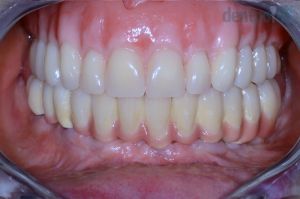

Implantációs hídpótlás

62 éves nő páciensünk előrehaladott fogszuvasodásokkal és csontpusztulással kereste fel rendelőnket. Sajnos ezek miatt egyik foga sem volt megtartható, így implantátumokra rögzített alsó körhíddal, ill. felső kivehető fogsorral pótoltuk hiányzó fogait. A fogeltávolításokat követően 6 héttel történt az implantáció és a csontpótlás. 6 hónap gyógyulást követően készültek el a végleges fogpótlások, azonban a csontosodás ideje alatt az implantátumokat azonnal terheltük, így a páciens rögtön a műtét után ideiglenes fogpótlásokkal távozhatott.

4) Esztétikus mosoly